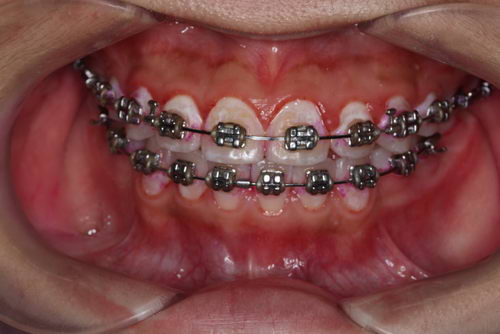

这是一位戴固定矫正装置的患者

第二张,这是仔细清洁之后的效果,但仍能能看到牙齿仍然有部分没刷干净的位置。像这种刷牙时有阻挡物的情况,如果不通过“穿针引线”式的清洁操作,牙缝根本就没法刷干净。